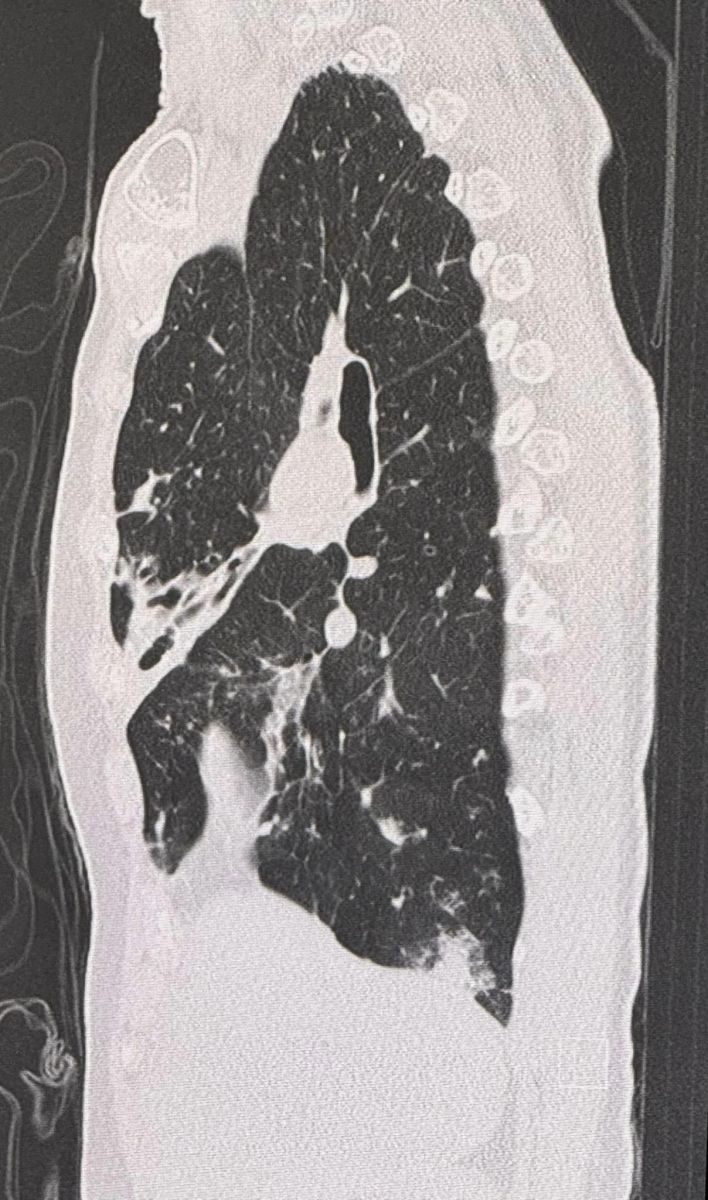

จากการตรวจร่างกาย ฟังปอดมีเสียงผิดปกติทั้ง 2 ข้าง เอกซเรย์ปอดผิดปกติเข้าได้กับหลอดลมโป่งพองทั้ง 2 ข้าง (ดูรูป) ทำคอมพิวเตอร์ปอดเห็นหลอดลมโป่งพองในปอดทั้ง 2 ข้าง (ดูรูป) ส่งเสมหะย้อมเชื้อหาวัณโรค AFB smear ให้ผลบวก วินิจฉัย: โรคหลอดลมโป่งพอง สงสัยติดเชื้อวัณโรค หรือวัณโรคเทียม จึงให้ยา INH,rifampicin,ethambutol รักษาวัณโรค ร่วมกับ azithromycin รักษาวัณโรคเทียม 2 สัปดาห์ หลังกินยาดีขึ้น หยุดไอ ไม่มีเสมหะ ผลเพาะเชื้อขึ้นเชื้อวัณโรคเทียม 3 ชนิด คือ M.fortuitum, M. intracellulare และ M. gordonae เมื่อทราบผลเพาะเชื้อได้หยุดยาทุกชนิดก่อน ขอเก็บเสมหะอีกครั้งแต่เก็บไม่ได้ เพราะไม่มีเสมหะ แนะนำให้หยุดการเทปุ๋ยรอบต้นไม้ในสวน